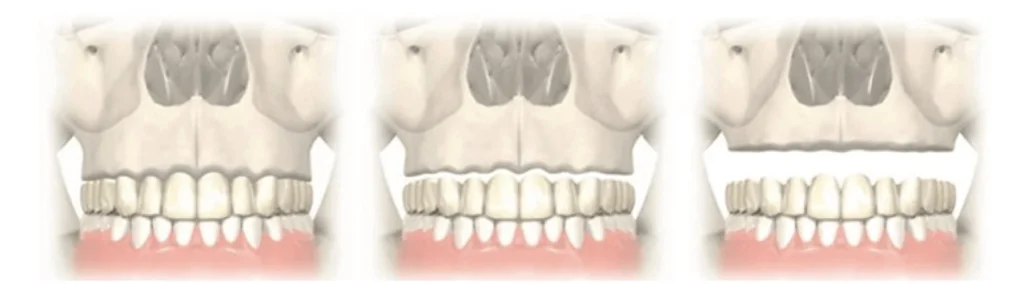

Si l’atrophie osseuse est seulement postérieure, 2 implants zygomatiques postérieurs suffisent couplés à 2 implants antérieurs classiques, on parle de réhabilitation prothétique fixe sur 4 implants de type zygomatique hybride. Dans ce cas de figure, l’implant zygomatique est positionné en position basse de manière à garder un volume osseux disponible supérieur sur le zygoma pour placer un 2 ème implant zygomatique à distance si besoin.

Si l’atrophie osseuse concerne toute la mâchoire, 4 implants zygomatiques sont nécessaires. Ils sont placés de manière à sortir sous les incisives latérales et les 2 ème prémolaires. L’implant supérieur longe à distance du rebord orbitaire, l’implant inférieur chemine sur la plus grande longueur d’ancrage osseux quelques millimètres plus bas. Le nerf infra-orbitaire responsable de la sensibilité para-nasale et jugale doit être respecté lors de la pose implantaire au risque de trouble de la sensibilité. On parle de réhabilitation prothétique fixe sur 4 implants zygomatiques ou quad zygomatiques.

La présence et le volume de fausse gencive sur votre prothèse dépendent de la quantité de perte osseuse verticale de votre mâchoire.

Pour compenser la perte osseuse verticale, une greffe osseuse peut être proposée mais impose plusieurs interventions, une durée allongée et un coût supplémentaire.

Le rajout de fausse gencive sur la prothèse est une alternative simple et esthétique. La jonction prothèse/gencive doit être plus haute que la lèvre au sourire pour ne pas être visible.